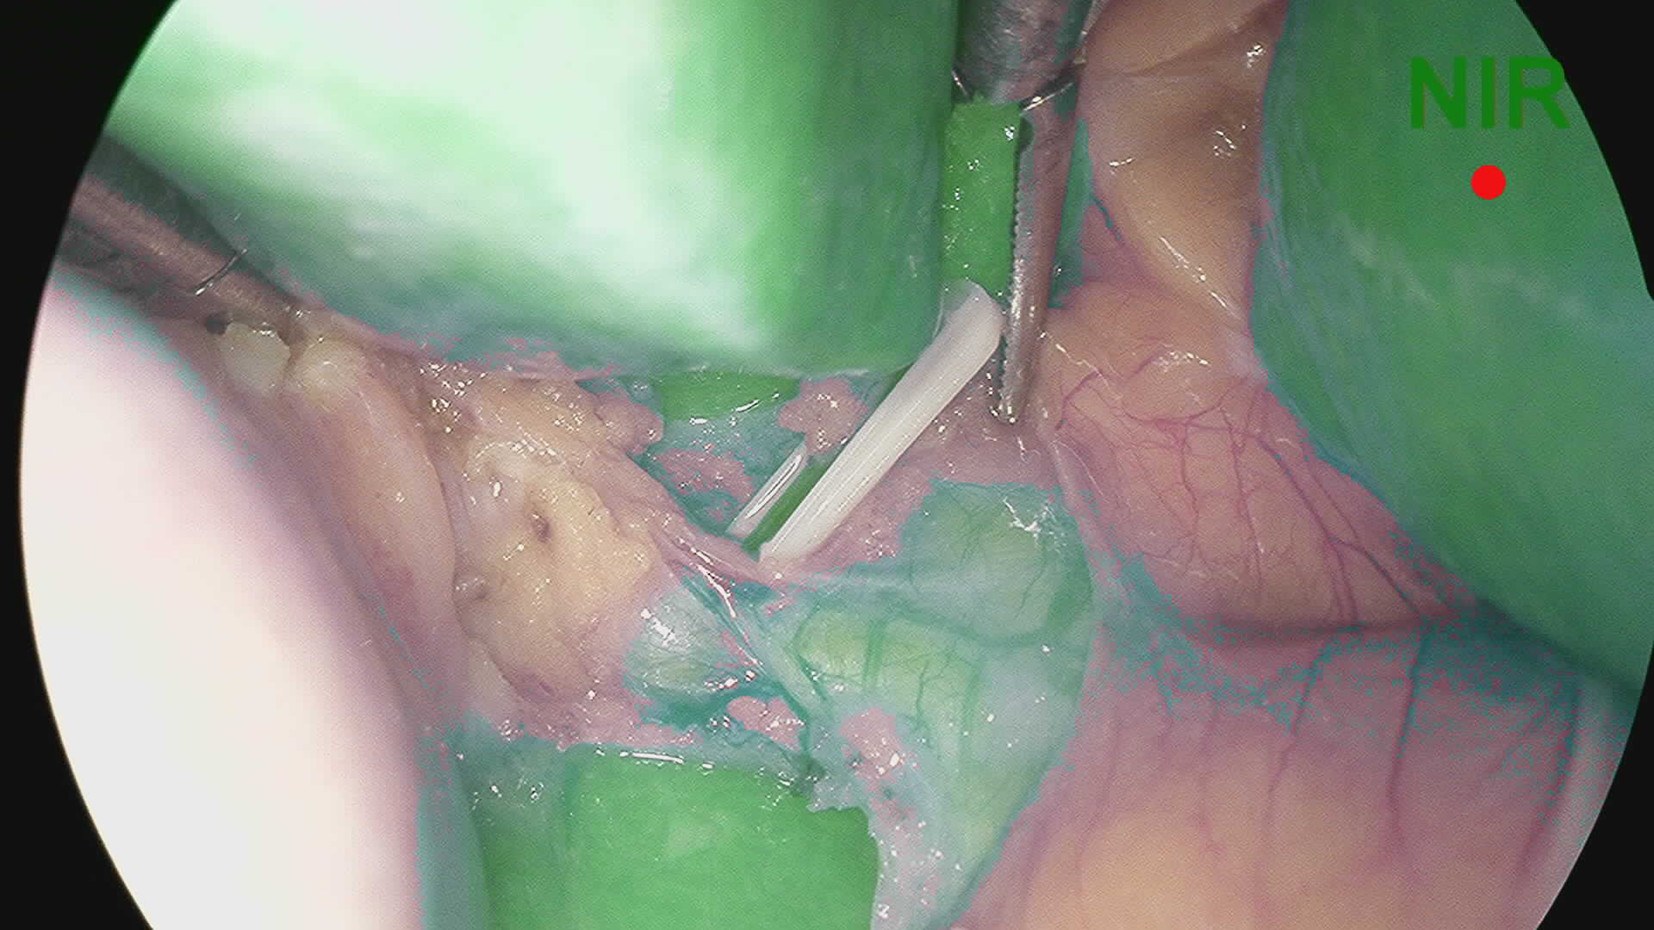

吲哚菁绿荧光显影在困难胆囊腹腔镜胆囊切除术中的应用价值

摘要:

目的  探讨吲哚菁绿(ICG)荧光显影在困难胆囊腹腔镜胆囊切除术(LC)中的应用价值。  方法  回顾性分析安徽医科大学第一附属医院2021年10月—12月行LC的患者临床资料,根据术中是否使用ICG荧光显影和是否为困难胆囊分为4组:A组为使用ICG荧光显影普通胆囊,B组为使用ICG荧光显影困难胆囊,C组为未使用ICG荧光显影普通胆囊,D组为未使用ICG荧光显影困难胆囊。比较各组手术时间、术中出血、住院时间、住院费用和术后并发症间的差异。正态分布的计量资料2组间比较采用t检验。计数资料2组间比较用χ2检验或Fisher确切概率法。  结果  A组与C组相比手术时间、术中出血、住院时间、住院费用和术中并发症,差异均无统计学意义(P值均>0.05)。B组手术时间和术中出血分别为(75.41±12.96)min和(18.27±6.97)mL,D组分别为(106.78±19.21)min和(23.99±8.43)mL,两组相比差异均有统计学意义(P值均<0.05);B组住院时间、住院费用和术后并发症与D组相比,差异均无统计学意义(P值均>0.05)。  结论  普通胆囊患者LC术中使用ICG荧光显影优势不明显;但在困难胆囊中,ICG荧光显影有利于胆道显露,可以缩短手术时间,减少术中出血。ZHANG Chao